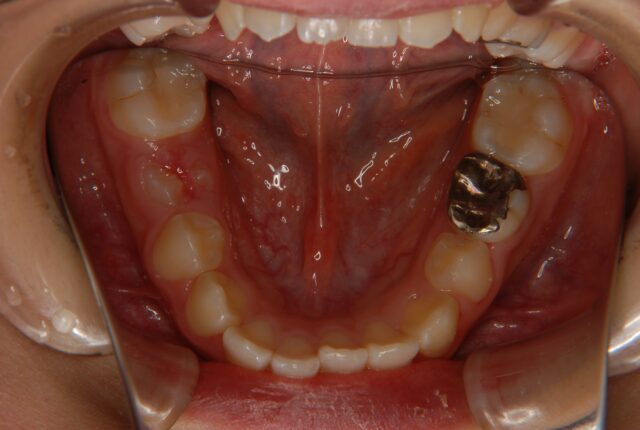

唇側矯正 小児矯正 反対咬合(受け口)の治療例【非抜歯】 この治療例は上下顎歯の唇側より矯正装置を装着して、反対咬合の改善を行った写真です。 治療前 治療後 主訴 受け口を治したい 診断名あるいは主な症状 下顎前突 年齢 10才 治療に用いた主な装置 唇側矯正装置 抜歯部位 非抜歯 治療期間 約2年 通院回数 24回 治療費概算 880,000円(税込) リスクと副作用 反対咬合を改善する時に上下の歯がぶつかり破折する可能性がある。下顎が後方に押し込まれ、顎関節に負担をかける可能性がある。